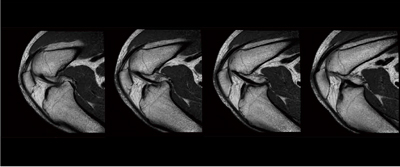

楕円形状のボアは,これまで困難であった撮像の可能性を広げます。楕円ボアの効果として,図2に示すように,肩関節などのオフセンター部位を撮像する際に,撮像部位を静磁場中心に移動できるため良好な脂肪抑制効果が得られ,高画質画像を得ることができます。また,自由な体位での撮像が可能で,まっすぐに寝ることが困難な被検者では,横になって撮像することも容易です。関節部の撮像では,図3に示すような膝関節の屈曲位など,大幅に拡大した左右方向のワイドボアを生かした撮像が可能です。

図2 楕円ボアの効果:肩関節の撮像例